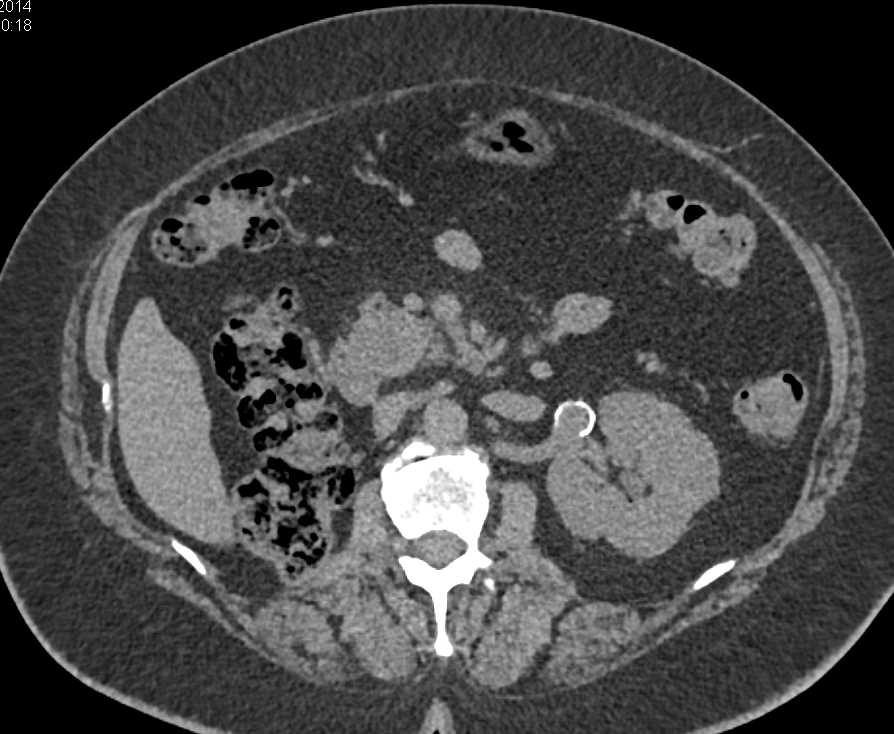

Recurrent Renal Cell Carcinoma Metastatic to the Pancreas, Contralateral Adrenal and Adenopathy